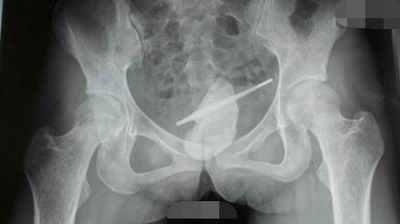

陕西宝鸡34岁的张女士听说温度计放入尿道可快速测体温,果不其然不慎将温度计滑进膀胱内,无奈跑医院做手术才取出。执刀医生说他从医20余年,遇过不少此类患者,曾取出过线绳、电线头等,温度计是头次见到。

不要以发烧测体温当借口嘛,明明是发骚!

还有,小编很好奇,电线头进去是准备测电压还是电流的,我读书少,请不要骗我。

目测“测体温”这个词又要被毁了。例句:热恋中的小明和小红今晚测了两次体温,彼此感觉舒服极了。

小编已申请专利——震动体温计,都别跟我抢!